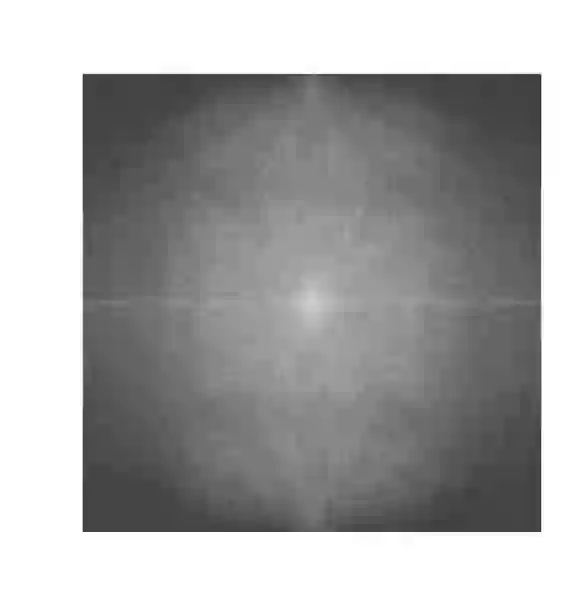

Objectives: Present a novel deep learning-based skull stripping algorithm for magnetic resonance imaging (MRI) that works directly in the information rich k-space. Materials and Methods: Using two datasets from different institutions with a total of 36,900 MRI slices, we trained a deep learning-based model to work directly with the complex raw k-space data. Skull stripping performed by HD-BET (Brain Extraction Tool) in the image domain were used as the ground truth. Results: Both datasets were very similar to the ground truth (DICE scores of 92\%-98\% and Hausdorff distances of under 5.5 mm). Results on slices above the eye-region reach DICE scores of up to 99\%, while the accuracy drops in regions around the eyes and below, with partially blurred output. The output of k-strip often smoothed edges at the demarcation to the skull. Binary masks are created with an appropriate threshold. Conclusion: With this proof-of-concept study, we were able to show the feasibility of working in the k-space frequency domain, preserving phase information, with consistent results. Future research should be dedicated to discovering additional ways the k-space can be used for innovative image analysis and further workflows.

翻译:提出磁共振成像(MRI)基于深层次学习的磁共振成像头骨剥离算法(MRI),该算法在信息丰富k-空间中直接发挥作用。材料和方法:利用来自不同机构的两套数据集,总共36 900 MRI片,我们训练了一个深层次学习模型,直接与复杂的原始K-空间数据合作。由HD-BET(Brain提取工具)在图像领域进行的Skull剥离过程被用作地面真相。结果:两个数据集都与地面真相非常相似(DICE分数92 ⁇ -98 ⁇ 和Hausdorff在5.5毫米以下的距离)。眼睛区域上的切片达到99 ⁇ 的DICE分数,而精度则在眼睛和下面区域下降,结果部分模糊。Kstrip的输出往往在头骨的标界边缘平滑。用一个适当的阈值创建了Binary面具。结论:通过这一检验研究,我们得以显示在K-空间频域内工作的可行性,保存阶段信息,并使用进一步探索K-空间图像的方法。